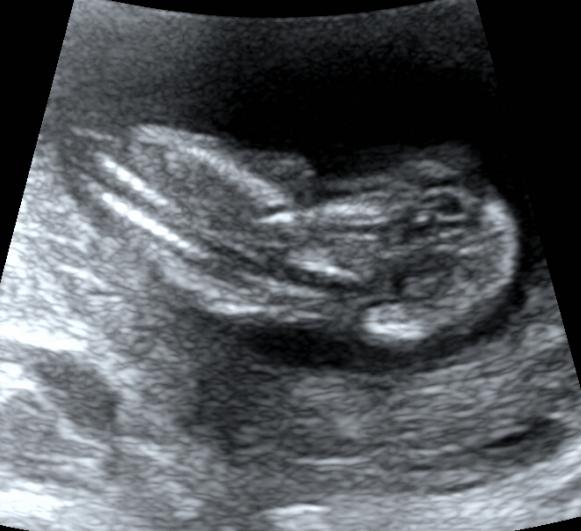

当然,这个时期我们除了重点观察TA的肢体以外,此时需要重点关注NT。

NT测量一般在11-13+6周内进行。

此时测量彩具有参考意义,但测量NT完全看宝宝的心情。

还有直接给个背影的。。。。